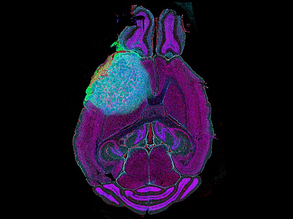

Beyond the Brain